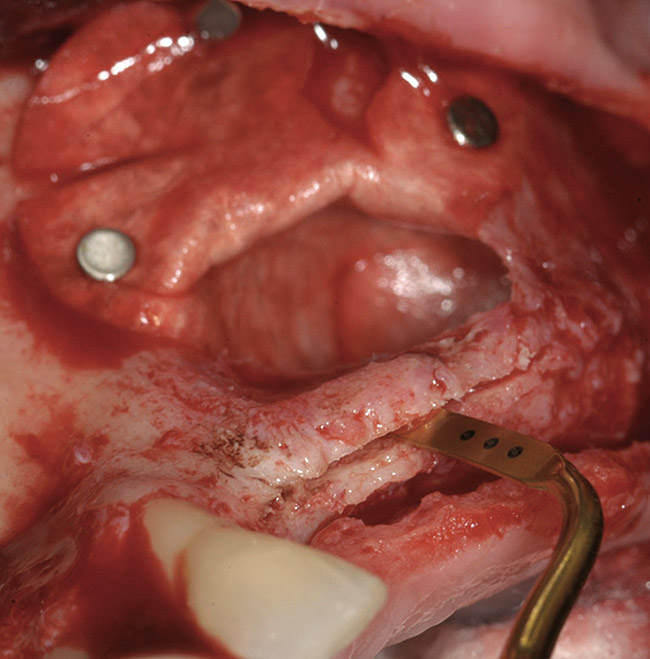

A 72-year-old man was referred for removal of failing maxillary right posterior implants (Figure 19). The treatment plan included removal of three implants with simultaneous bone augmentation and replacement implants for implant-supported fixed bridgework. Implant removal and bone grafting with rhPDGF (Gem 21®, Osteohealth, www.osteohealth.com) and allograft (MinerOss) and xenograft (BioOss®, Geistlick, www.geistlickonline.com) were used along with titanium mesh for space maintenance (Figure 20, Figure 21 and Figure 22). Six months later, mesh removal revealed type I bone allowing for placement of three implants (Figure 23 and Figure 24).

Figure 20  Removal of the failing implants.

Figure 20

Figure 21  Bone grafting with rhPDGF, allograft, and xenograft.

Figure 21

Figure 22  Titanium mesh fixation.